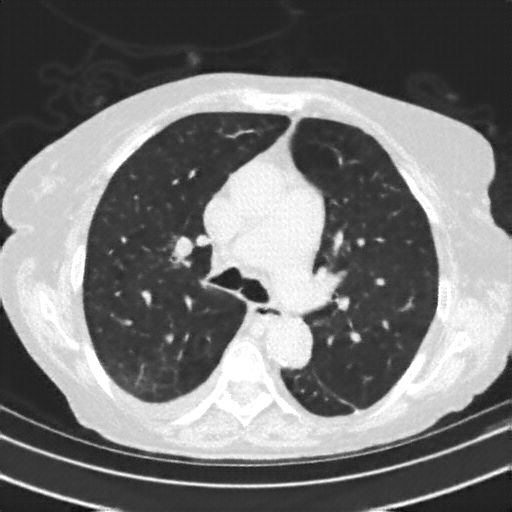

Reconstructed NATIVE CT scan (cycle consistency)

Full window (WL 1023.5, WW 4095 β†’ Low βˆ’1024, High +3071)

Lung window (WL -600, WW 1500 β†’ Low βˆ’1350, High +150)

Mediastinum window (WL 40, WW 400 β†’ Low βˆ’160, High +240)